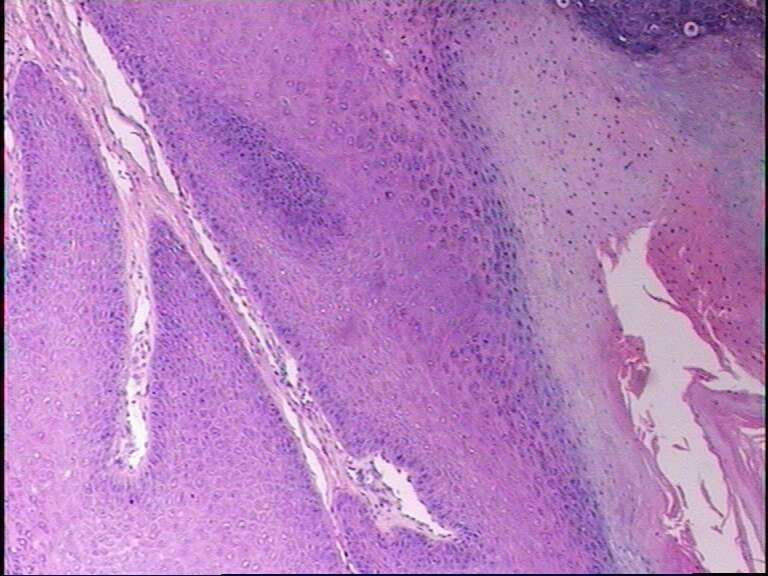

男38岁,手指肿物一年

寻常疣

最后一张典型的寻常疣构型

寻常疣 肉眼间 皮肤局限性乳头状突起新生物。

镜下 表皮棘层增生,颗粒层增厚,角化亢进及角化不全,真皮乳头瘤病。颗粒层细胞空泡变性,其核内或胞质内有均质性嗜酸性蛋白小体形成,周围有空晕。角化不全的细胞科堆积成小山包样外观。

乳头瘤样增生,空泡化细胞,典型寻常疣!最后一张典型的寻常疣构型!

典型的寻常疣病理改变。